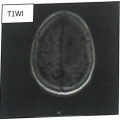

| Imaging:(Click to enlarge) | 患者胸部 CT检查:胸廓两侧基本对称,两肺纹理增多,气管及各叶、段支气管管腔通畅。支气管壁增厚。左肺见囊状薄壁透亮影。两肺散在斑片状密度增高影。两侧肺门结构清楚,两侧肺门旁及纵隔内未见明显肿大淋巴结。纵隔居中,心包未见增厚及积液;心脏饱满,主动脉及冠状动脉壁见斑点状致密影。两侧胸膜未见异常,两侧胸腔见窄弧形积液。 检查结论:两肺散在炎症;左肺肺大泡。 患者 MRI检查:左额叶见多发结节状异常信号影,大者位于颅板下,大小约2.6cmx1.6cmX2.8cm,T1WI呈低等信号,T2W!呈不均匀稍高信号,边缘 DWI 呈高信号,ADC 呈低信号,边界欠清楚,增强后病灶明显环形不均匀强化,周围见环形T1WI低、T2WI高信号水肿带。 检查结论:左额叶多发占位(较前2025-08-09片范围增大),考虑恶性肿瘤,转移瘤待排,请结合临床,建议进一步PET-CT检查。